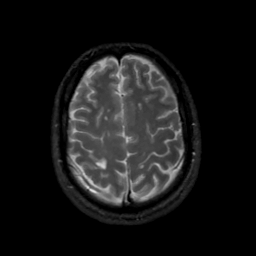

MR Study #16, June 23, 1991 -- Slice #39

[Home][Help][Clinical][Tour 1][Tour 2] Slice 39